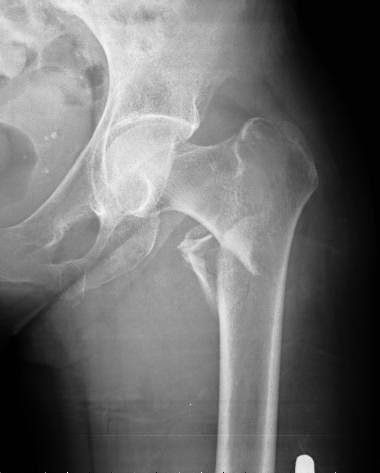

Osteoporosis: umbrales de intervención adaptados a cada país

Una revisión sistemática de los umbrales de intervención basados en la herramienta FRAX para la estimación del riesgo de fractura. Archives of Osteoporosis, 27 de julio de 2016

- Traumatología